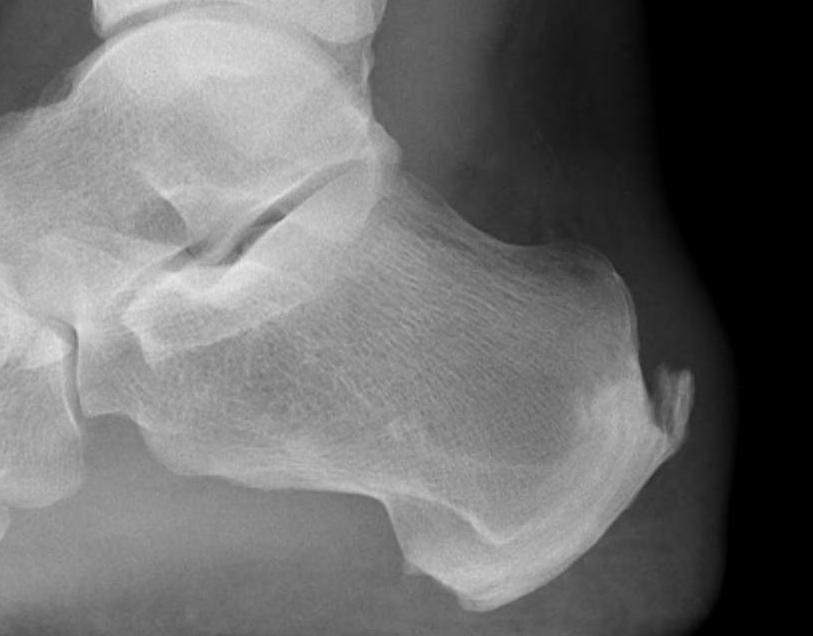

X-ray

Insertional achilles tendon spurs

- also present in asymptomatic patients

Calcification of bone-tendon interface with spur

Haglund's Deformity

- bony protuberance of posterosuperior calcaneus

Pavlov's parallel pitch lines

- lateral weight bearing x-ray

- draw parallel pitch lines

- defines Haglund's deformity to be removed (above second line)

Fowler's angle - Normal < 70° / Abnormal > 80°